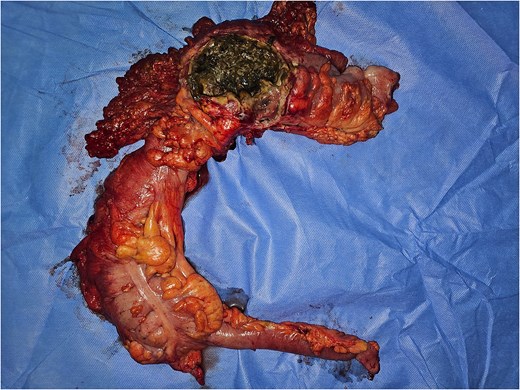

Emergency laparotomy revealed a large sealed perforation of the mid-transverse colon adherent to the first jejunal loop and omentum, purulent peritoneal effusion, and a fibrotic, inflamed duodeno-pancreatic block. The remainder of the gastrointestinal tract was unremarkable. A right extended hemicolectomy with double stoma, retroperitoneal lavage, and multiple drainages was performed (Figs 3–6).

Image of the surgical specimen of a right hemicolectomy showing the perforation.